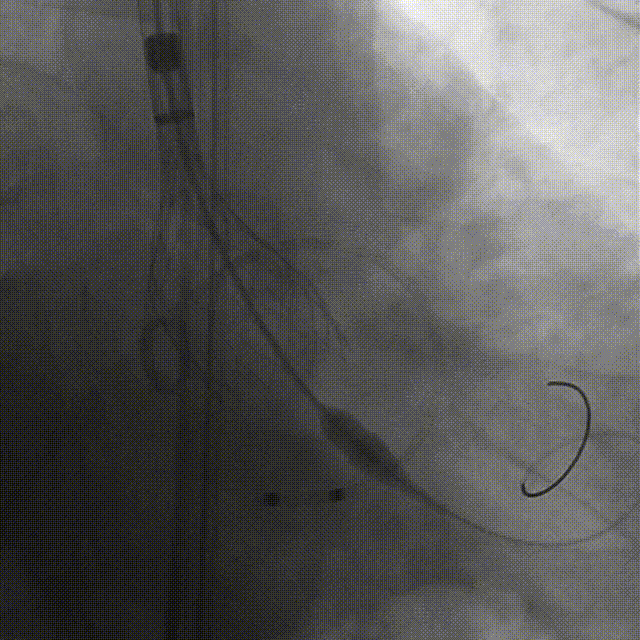

谷兴华教授 山东大学齐鲁医院 锚定终身获益,重视首次干预选择:心脏瓣膜病介入中心成立2年多来,中心核心目标始终保证在解决即刻病症的基础上,护航患者的全生命周期健康管理。 摆在眼前的实际是日益年轻化的患者群体,这意味着我们从手术伊始,就必须将患者未来数十年的生活质量和再次干预风险纳入核心考量,主动规划长远的健康路径。此次患者选择更具耐久的新型干瓣技术,力求减少患者未来再次干预的风险。同时,通过“TAVR+PCI一站式手术”这样的团队协作模式,系统性地处理多重心血管问题,避免分次手术的负担与风险,这正是我们中心一直秉持的“心脏瓣膜病全生命周期管理”理念的实践。让我们一起探索从“治已病”真正迈向“管长远”,让更多的患者获益! 病例特点速览 本次救治的患者,病情呈现“基础病交织、多病变叠加、锚定风险高”三大核心特征。患者为65岁,女性,病变特点TypeI型二叶瓣、轻度钙化,锚定风险大;同时患有冠状动脉粥样硬化性心脏病、慢阻肺(COPD);既往有长期吸烟饮酒史、脑梗死病史、高血压病史、乙肝小三阳病史及腹股沟疝修补手术史,患者STS评分9.32%,外科手术高危,经齐鲁医院瓣膜中心团队评估认为:局麻下“一站式TAVR+PCI”为最优治疗方案,结合患者较年轻,可选择具有长期耐久性的干瓣。 患者病史 主诉:活动后胸闷、憋喘余,加重20余天 既往史:30年前确诊乙肝小三阳,否认其他传染病史;有右腹股沟疝修补手术史,高血压病史,近期规律服药控制。 现病史:患者1年前出现活动后胸闷、憋喘,休息可缓解,为进一步诊治。2月前因“突发意识模糊、口齿不清”于当地医院入院,诊断为“急性脑梗死”,予以微创介入取栓治疗,恢复可,未遗留后遗症。20天前于当地医院再次入院行脑血管支架植入术,术后出现胸闷、憋喘,伴大汗,行心脏超声提示主动脉瓣重度狭窄,并行冠脉造影检查,予以药物治疗。10天前就诊于我院复查心脏超声提示二叶式主动脉瓣,主动脉瓣狭窄(重度)并反流(轻度)。患者现仍感胸闷,双上臂疼痛不适,咳嗽咳痰,日常活动受限。为行进一步治疗就诊于我院,门诊以“主动脉瓣狭窄、冠状动脉粥样硬化性心脏病”收入院; 个人史:吸烟50年,饮酒50年; 体格检查:体温:36℃,脉搏:67次/分,呼吸:18次/分,血压:143/76mmHg; 术前超声提示: 二叶式主动脉瓣主动脉瓣狭窄(重度)并反流(轻度);升主动脉扩张、左心扩大三尖瓣反流(少量);左室充盈异常;CW测最大压差86mmHg,平均压差43mmHg,最大血流速度463cm/s,连续方程法估测主动脉瓣口面积0.78cm² 术前CT评估 Type1型二叶瓣,轻度钙化、左右融合,主动脉瓣环径25.3mm,LVOT直径25.5mm,鱼嘴空间约26.6mm,主要靠瓣环锚定。窦部空间大、左右融合,VTC空间足够,无冠脉风险 ;左室内径正常,主动脉瓣环水平夹角49.6°。外周双侧入路内径可,髂外动脉存在散在钙化、双侧入路能够支持20F大鞘通过,右股低分叉,主动脉弓距弓角可。 个性化手术策略:局麻一站式方案+创新瓣膜精准适配 入路选择:主入路:右侧股动脉(右股分叉上方1cm处穿刺);辅入路:左侧股动脉;器械:20F大鞘; 手术流程规划:局麻下行同期一站式TAVR+PCI,植入ProStyle A®预装干瓣; 瓣膜选型与预处理:瓣膜型号:ProStyle A® AV32;不预扩; 定位与释放方案:初始定位:瓣上3mm处释放,瓣膜自然下滑至工作位,最终目标“0-瓣下5mm位”。 手术过程:局麻一站式操作+创新瓣膜植入,无缝衔接 手术团队按预设方案稳步推进,实现TAVR、PCI与ProStyle A®干瓣植入的无缝衔接: 1.术前准备:完成影像评估、血管通路建立,确认ProStyle A® AV32瓣膜状态; 2.PCI治疗:通过主入路完成左冠造影,前降支、对角支明显狭窄,精准植入两枚支架,恢复冠脉血供; 左冠造影,前降支、对角支病变 PCI后造影,病变血管充盈良好 3.主动脉根部造影:确认主动脉根部解剖结构,并精准跨瓣; 主动脉根部造影 精准跨瓣 4.干瓣植入:将瓣膜输送过弓、过瓣,并精准定位; 输送系统柔顺过弓 精准定位 5.术中评估:释放瓣膜至工作状态,再次造影评估,位置满意,完全释放瓣膜; 工作位评估 32号瓣膜稳定脱钩 6.释放后造影:可见瓣膜位置满意、形态良好,无明显瓣周漏。 最终造影,位置形态良好,无瓣周漏 术后超声探查:位置(瓣下4mm)、形态良好,无瓣周漏,PGmean=10mmHg。 此次手术的成功,体现了山东大学齐鲁医院心脏瓣膜病介入中心秉承的“心脏瓣膜病全生命周期管理”的理念和团队协作的临床能力。面对低龄高风险复杂病例,团队通过术前充分评估、术中精细操作,结合具有长期耐久性的干瓣技术,以一站式方案改善患者症状、提高生活质量并延长寿命,为类似病例的诊疗提供宝贵经验。 专家简介 谷兴华 山东大学齐鲁医院(点击查看专家详细简历)